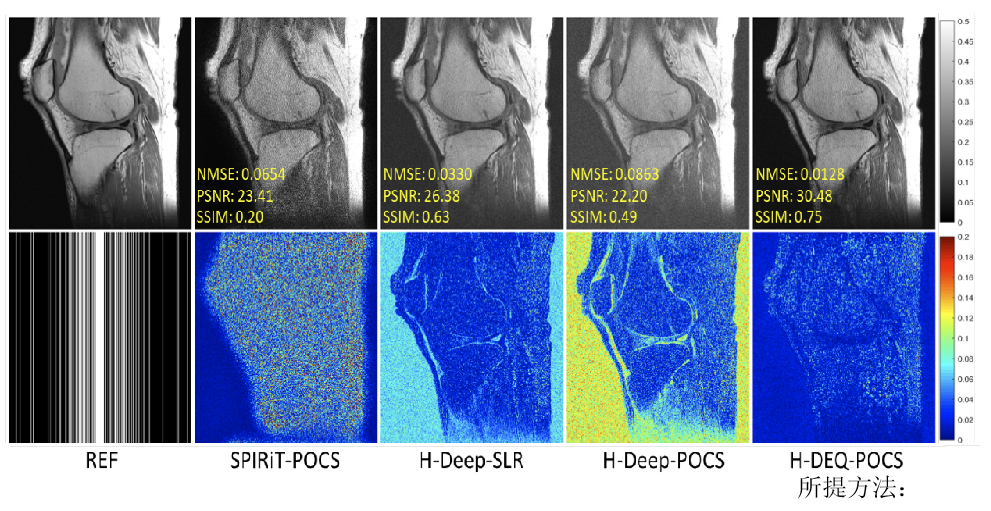

其次,针对现在主流深度学习快速重建方法可靠性不足的问题,提出了零阶算法展开网络的思想,利用网络表示正则化子零阶信息(正则化子本身),增强了网络学习的可解释性,保证了网络算法收敛性和鲁棒(正则)性。实验证明(图2),该方法重建图像质量明显优于传统方法。研究成果发表在医学成像领域著名期刊IEEETransactions on Medical Imaging。

图2.测量噪声扰动下,4倍加速重建结果